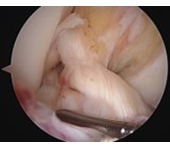

半月板損傷

半月板部分切除

中高年者の膝の痛みの中には、投薬、注射やリハビリなどの治療を受けても効果が見られないことがあります。このような場合、半月板損傷や関節軟骨損傷(関節内遊離体)が原因になっていることがあります。半月板損傷や、関節軟骨損傷は、レントゲン検査では判明しにくいためMRI検査を行い、検査で異常が認められる場合には、小さな切り口で大きな効果が得られる関節鏡視下手術をおすすめします。

関節鏡の手術の傷は、約5mm程度のものが2か所で、ほとんど目立ちません。また入院も数日~1週間程度で、職場復帰も比較的早く可能です。